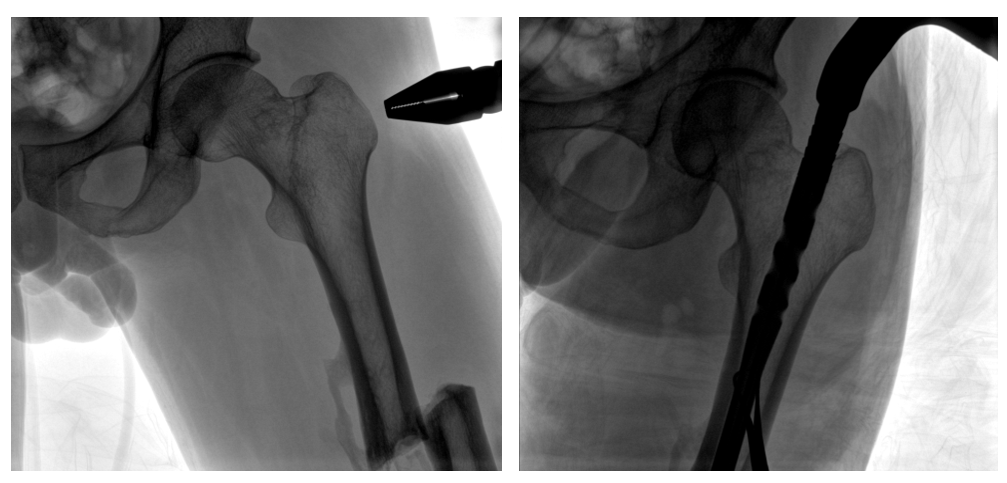

病例二:

患者左股骨干完全骨折,經過醫生評估,使用“髓內釘內固定術”進行治療。髓內釘內固定術需要將入釘點至骨折部位的影像完全展示,在一些長骨的骨折中,對視野范圍要求高。

一體式C形臂釘點至骨折部位的臨床影像

在進行髓內釘內固定術時,醫生需要同時觀察到入釘點和骨折部位的情況,PLX119C大平板一體式C形臂能夠呈現更廣闊的成像面積,滿足大部分長骨髓內釘內固定術的攝片需求。